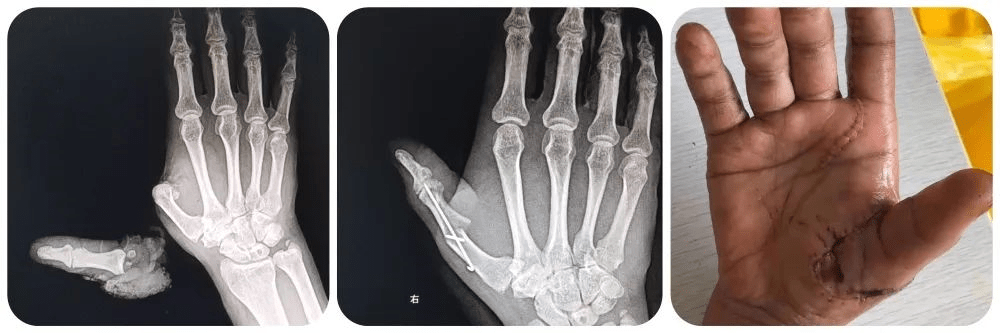

手指再造了解一下!_进行_功能_患者

图片尺寸1000x333

因外伤损伤右手示,中,环指,在当地医院行"右手示,中,环指残端修复术"

为患者进行了检查,患者大拇指已经完全离断,而且残端又被切成了两份